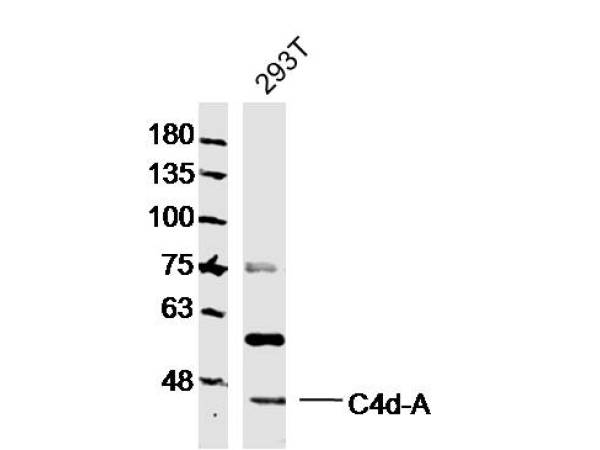

C4d-A Polyclonal AntibodyBS-10453R

ApplicationsImmunoFluorescence, Western Blot, ELISA, ImmunoCytoChemistry, ImmunoHistoChemistry, ImmunoHistoChemistry Frozen, ImmunoHistoChemistry Paraffin

ReactivityHuman, Mouse

TargetC4A